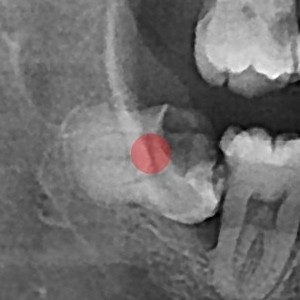

智齿拔除 严重龋坏的智齿